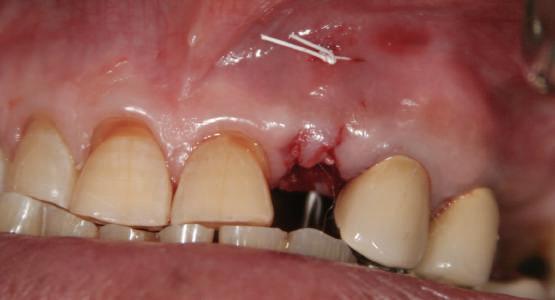

Alt caz (1) Figurile

4. După osteointegrarea implantului 2.4., s-a observat recesia în etapa de amprentare a implantului 2.5.; s-a decis reprepararea marginilor bontului individualizat CAD/CAM 2.4. Înainte de preparare s-a aplicat şnur de retracţie pentru a evita lezarea ţesutului şi a îmbunătăţi vizibilitatea dintelui 2.3. şi a marginii bontului implantar individualizat. Aşa cum era de aşteptat, recesia a fost mai mare de-a lungul versantului distal al bontului 2.4. adiacent locului de extracţie vindecat/cu implantul mai nou.

5. Bontul individualizat aplicat (2.5.) cu bontul repreparat anterior (2.4.). Nu a survenit recesie nouă de o perioadă de peste 3 ani.